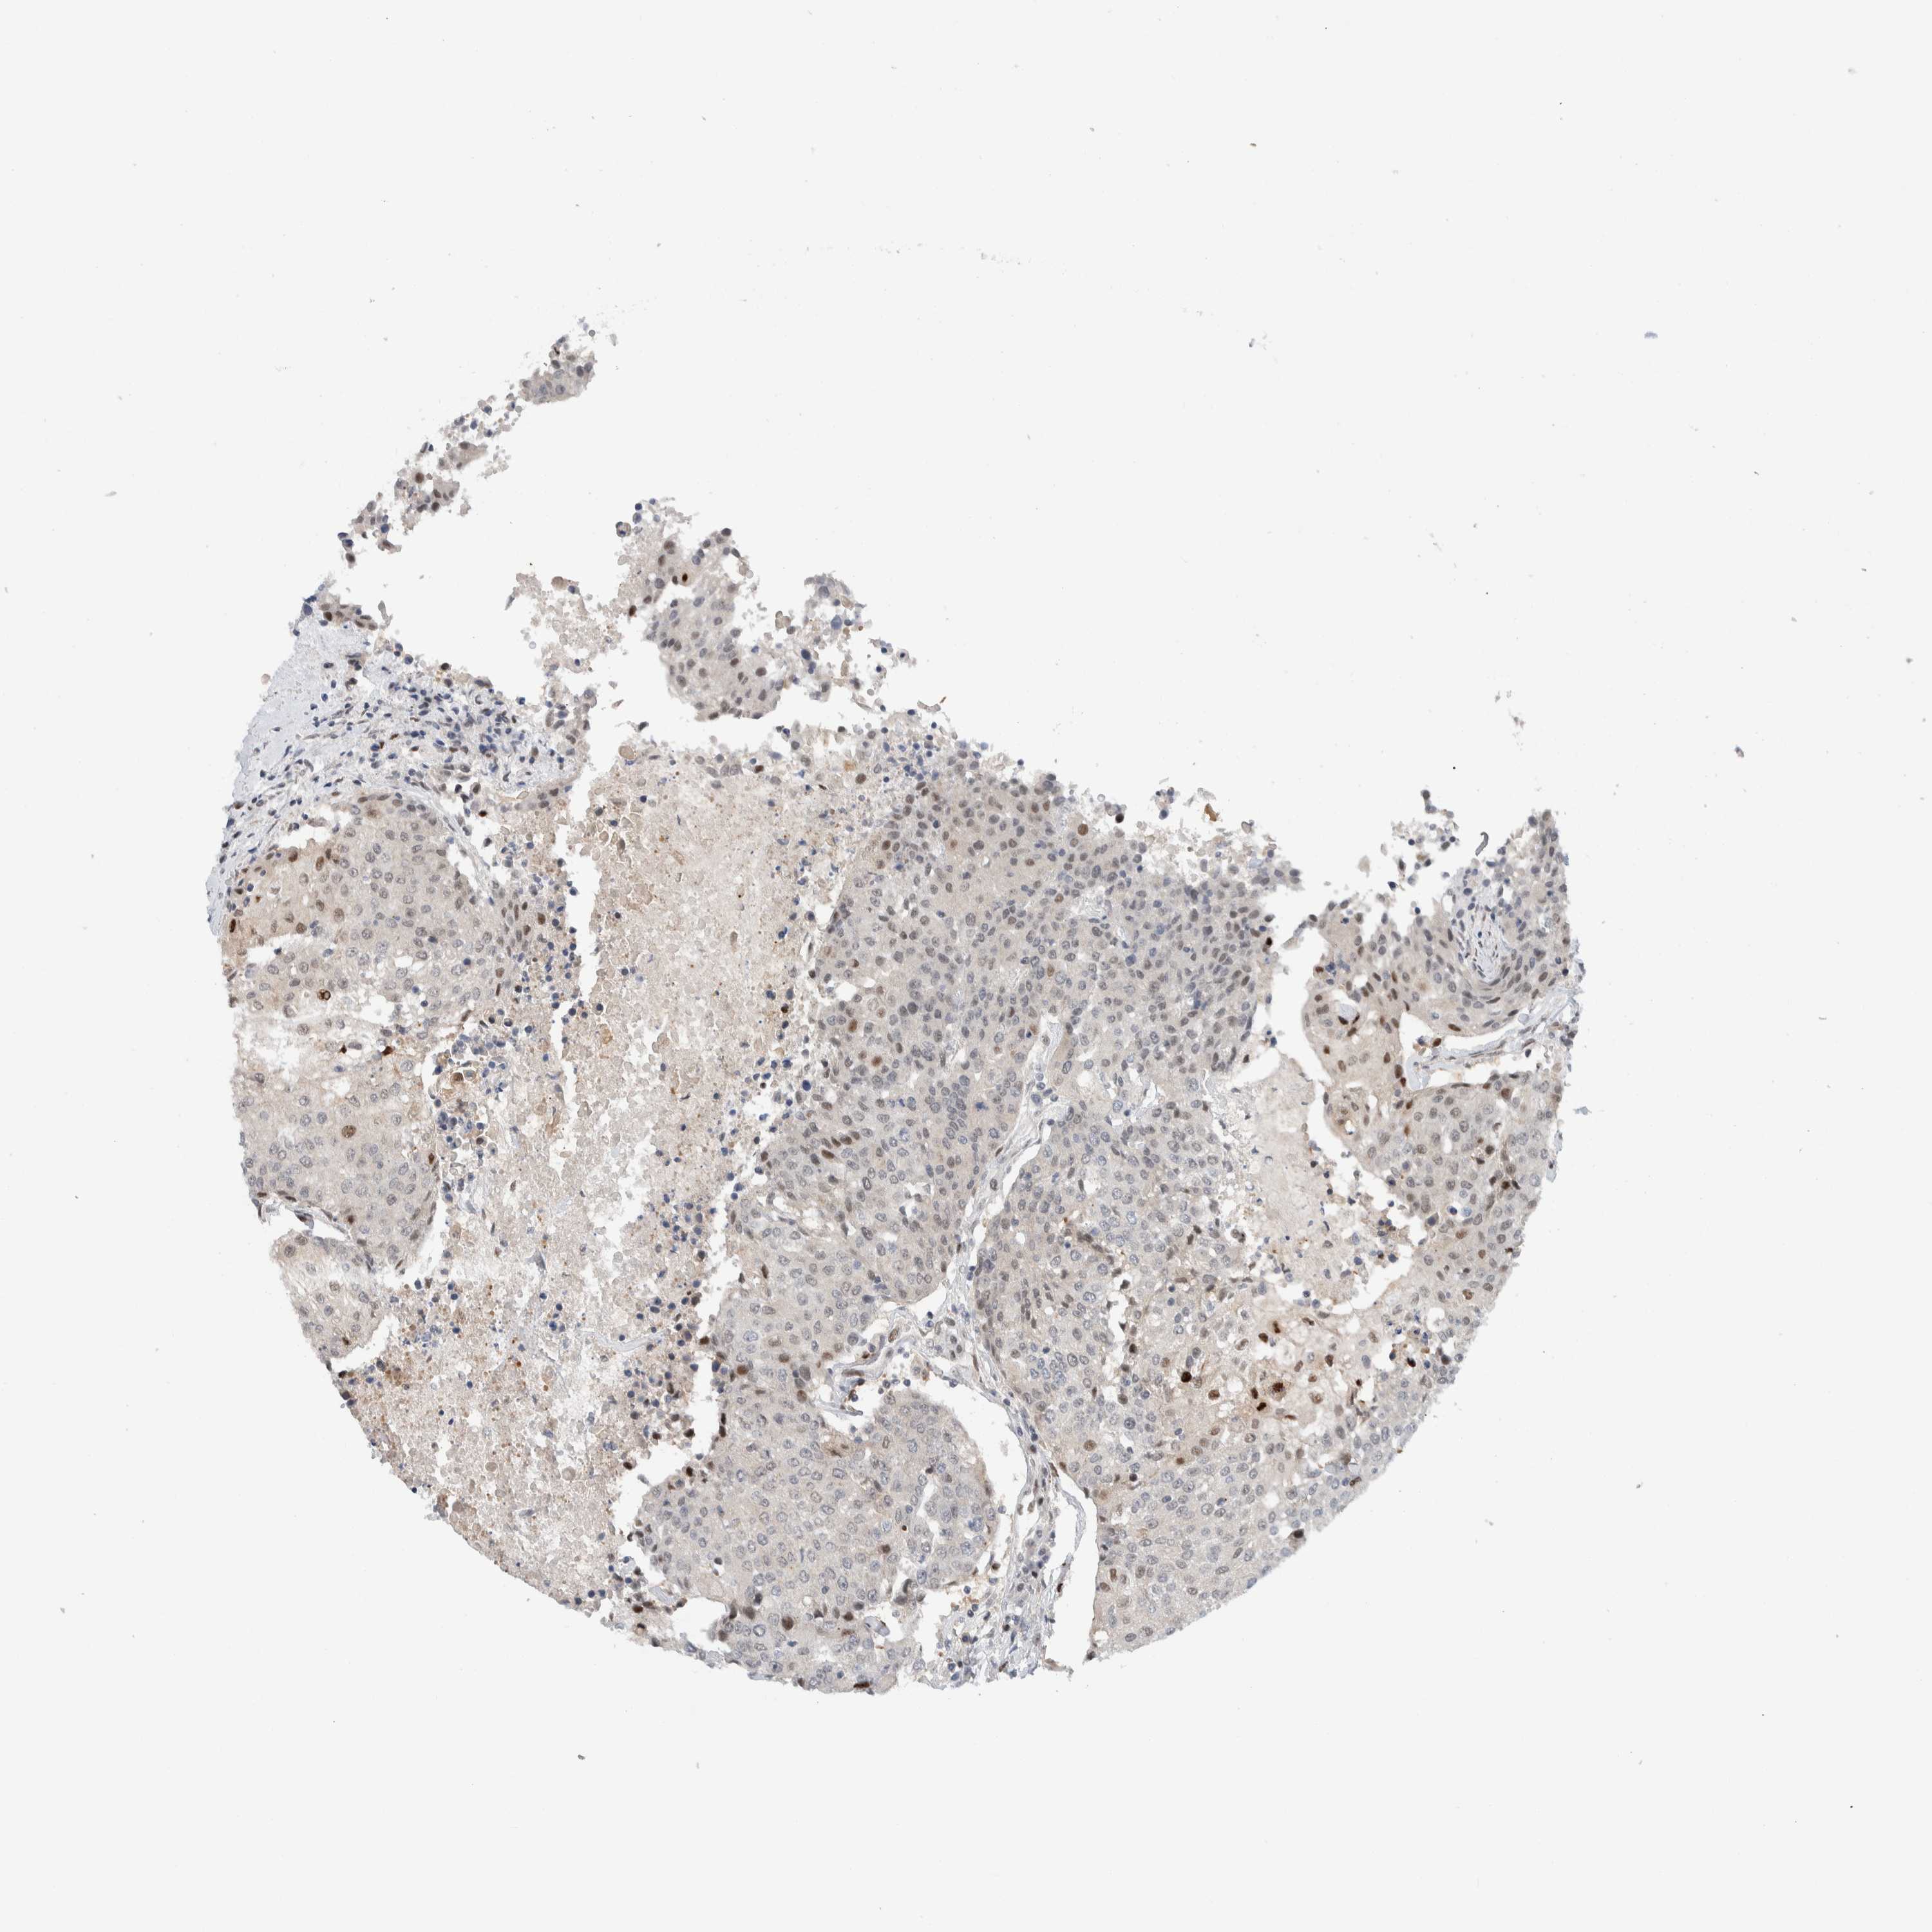

UROTHELIAL CANCER - Protein expressioni

A mouse-over function shows sample information and annotation data. Click on an image to view it in a full screen mode. Samples can be filtered based on level of antibody staining by selecting one or several of the following categories: high, medium, low and not detected. The assay and annotation is described here.

Antibody stainingi

Antibody staining in the annotated cell types in the current human tissue is reported as not detected, low, medium, or high, based on conventional immunohistochemistry profiling in selected tissues. This score is based on the combination of the staining intensity and fraction of stained cells.

Each image is clickable and will lead to virtual microscopy that enables deeper exploration of all samples and also displays staining intensity scores, fraction scores and subcellular localization as well as patient and tissue information for each sample.

Antibody HPA024137

Staining

High

Medium

Low

Not detected

Intensity

Strong

Moderate

Weak

Negative

Quantity

>75%

75%-25%

<25%

None

Location

Nuclear

Cytoplasmic/membranous

Cytoplasmic/membranous,nuclear

Urothelial carcinoma, Low grade

Urothelial carcinoma, High grade